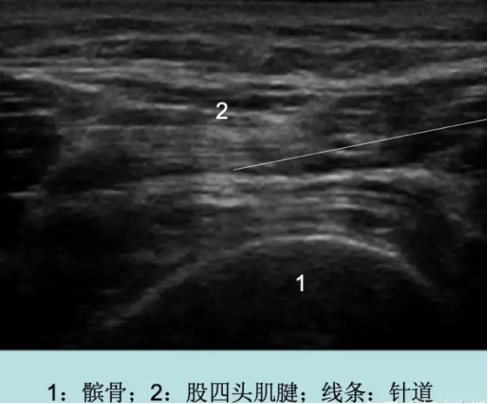

确认病因后,邓阿茂主任决定使用肌骨超声引导下的精准治疗技术为主分期综合为患者进行对症治疗。在肌骨超声引导下精确将关节积血抽出,同时将生理盐水等治疗性药液注射在病灶处,从而最大限度地减少了关节内在的压力,提高了治疗的精准度和效果。经过大约20分钟的治疗后,患者右膝的胀痛与活动度改善。

图片